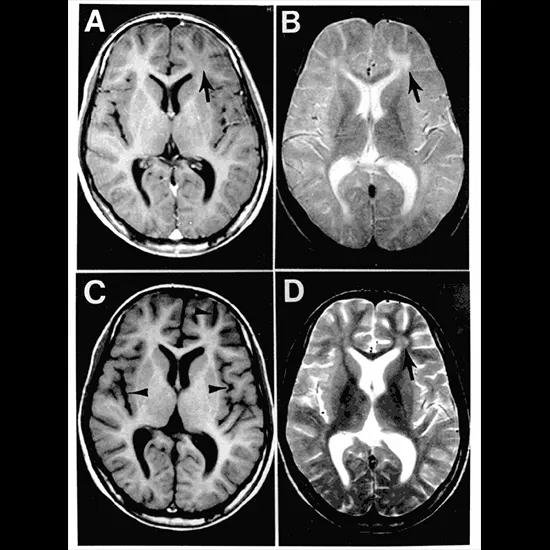

A specialist suspects subacute sclerosing panencephalitis in youthful individuals who have mental weakening and muscle jerks and a past history of measles. The diagnosis may be affirmed by examination of cerebrospinal liquid, a blood test that uncovers tall levels of counter acting agent to the measles infection, by an anomalous electroencephalogram (EEG), and by attractive reverberation imaging (MRI) or computed tomography (CT) that appears brain variations from the norm.

- Brain MRI